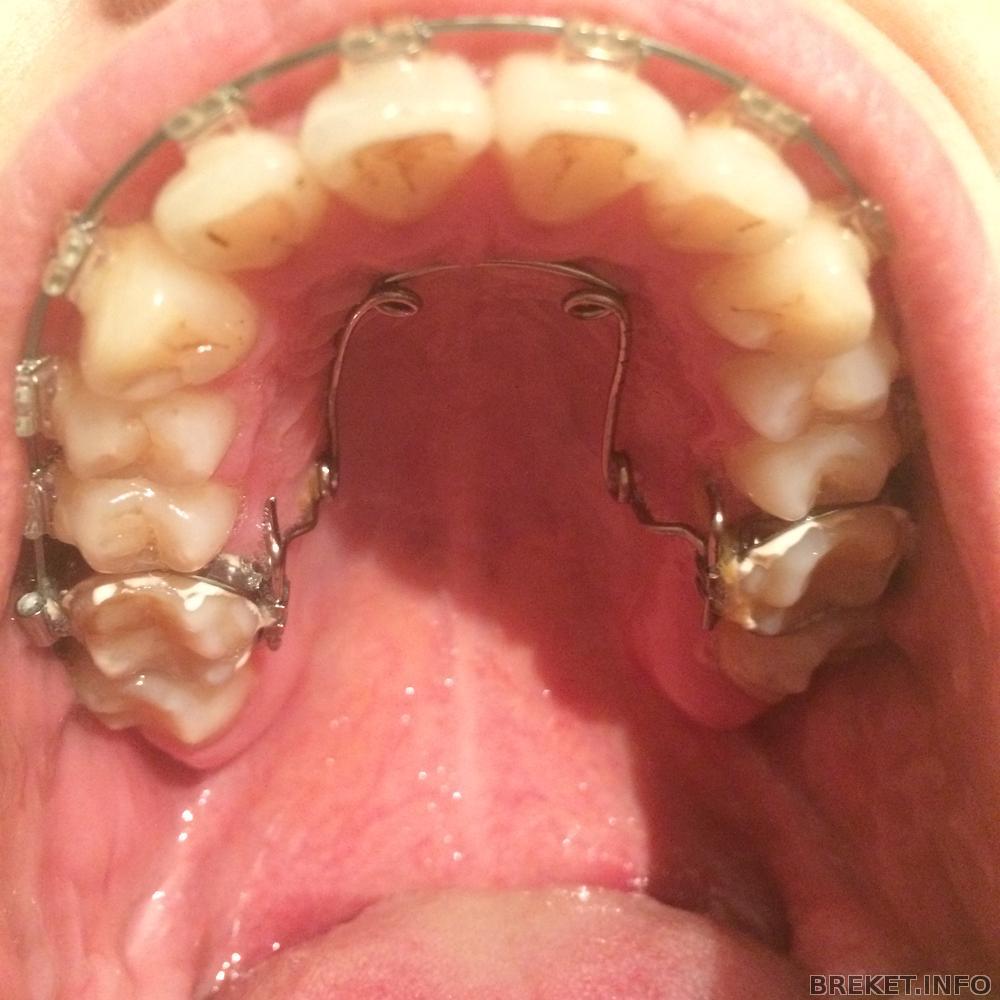

Установили квадхеликс

Ксеничка, да, это штука для расширения челюсти, сфотаю попозже. если честно, ожидала, что будет прям больно сильно, готовилась к худшему, начитавшись отзывов. но было не так больно и сейчас меня этот аппарат не так сильно беспокоит, как брекеты, которые мне наклеили с внутренней стороны нижней челюсти, чтоб цеплять за них тяги. вот эти девайсы мне раздирают язык, не могу из-за них кушать, хотя уже прошло больше недели(((

Ксеничка, хожу с брекетами уже 1 год и 9 месяцев. пару месяцев назад орт говорил, что скоро будем снимать))) а вот недавно вдруг решил, что мне надо расширять зубные ряды, так как прикус не становится таким, как должен быть((( я тут плакалась в предыдущем посте. но ничего не поделаешь((